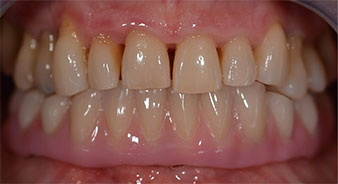

La paziente, 64 anni, presenta una dentatura residua di denti 38, 33 e 43 e una protesi combinata innestata nella mandibola (Fig. 1 e 2).

Una volta trascorso il tempo necessario per la osteointegrazione, è stato possibile prendere l'impronta definitiva degli impianti e, poi, è stata realizzata la protesi definitiva (Fig. 19 e 20). A questo punto, il dentista e la paziente hanno potuto decidere insieme se utilizzare delle faccette in ceramica o in vernice acrilica, con una struttura in zirconio o metallo. In questo caso, il Dott. Pascu e il suo team hanno preferito delle faccette in vernice acrilica, a seguito della prognosi difficile sulla dentatura mascellare e sulla posizione allungata del dente 24. Questo tipo di faccette è solitamente molto più facile da adattare e, di conseguenza, può essere modificato per rispondere alla nuova situazione della mascella.